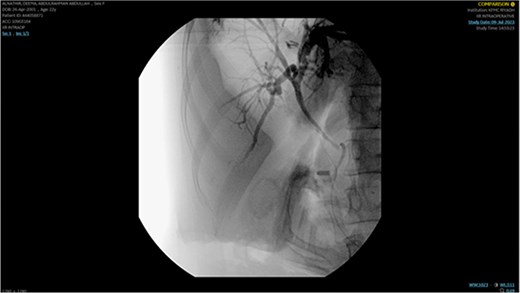

The remaining hepatic parenchyma had homogenous enhancement and smooth outlines. As shown in Fig. 4, the Endoscopic retrograde cholangiopancreatography (ERCP) was performed using double-guided wire and successfully resulted in bile duct cannulation.

Endoscopic retrograde cholangiopancreatography (ERCP): Demonstrating the cannulation procedure and the placement of the cannula.